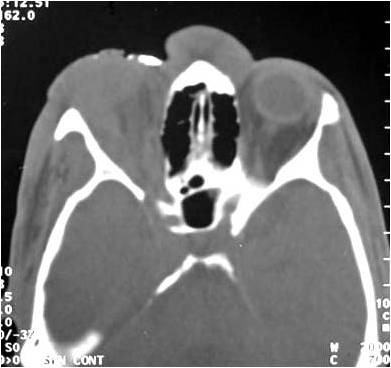

Radiograficamente, além do planejamento para os implantes, são avaliados todo o trajeto do nervo alveolar e a posição do forame mentoniano, utilizando-se da ortopantomografia, ou ainda de tomografia computadorizada (16).

Pode-se com isso fazer um traçado predicativo do local das osteotomias e, na tomografia, avaliar densidade do osso medular, a espessura das corticais e, as medidas precisas da posição do canal mandibular em todo seu trajeto

Estudo radiográfico perfeito para a concretização da manobra cirúrgica, levando-se em consideração todos os detalhes da localização do plexo alveolar inferior e suas relações anatômicas (Figs. 2 e 3).

Figs. 2 e 3 – Aspecto radiográfico mostrando a perfeita localização do plexo alveolar inferior com as medidas corretas para a manobra cirúrgica com a localização do implante.